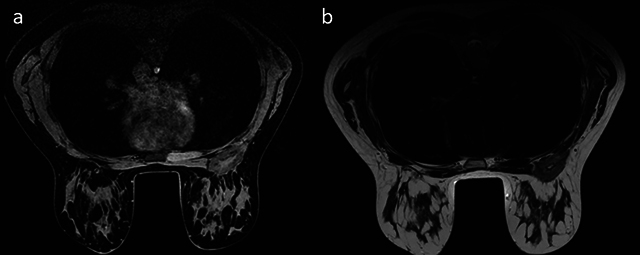

Silicone gel-filled breast implants are widely used for breast augmentation and reconstruction after mastectomy. However, there are some known complications associated with silicone implants: Leakage and migration of silicone particles from the implant cause a granulomatous reaction. Granulomas may present as masses with features of malignancy on breast MRI. We present a case of a giant breast siliconoma in a woman who had undergone reconstruction with breast prostheses, which were surgically removed because of rupture 8 years ago. Teaching point: Despite increasingly efficient diagnostic tools, siliconoma diagnosis remains challenging.

硅凝胶填充乳房假体广泛用于乳房切除术后的隆胸和重建。不过,硅胶假体也有一些已知的并发症:硅胶微粒从植入物中渗漏和迁移会引起肉芽肿反应。肉芽肿在乳腺核磁共振成像中可能表现为具有恶性肿瘤特征的肿块。我们介绍了一例巨大乳腺硅胶瘤病例,患者曾接受过乳房假体重建手术,8 年前因假体破裂而被手术取出。教学要点:尽管诊断工具越来越有效,但硅胶瘤的诊断仍然具有挑战性。